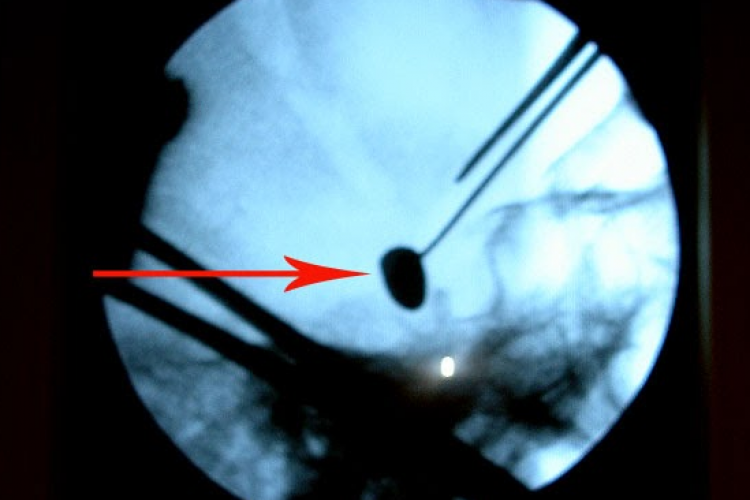

„ Я сделал операцию по интраоперационной рентгенографии. С трудом обнаружил пулю, потому что она находилась в мозге на очень большой глубине. Мой успех как нейрохирурга был не только в удалении пули, но и в том, что пациент после операции смог стать на ноги, смог сидеть. Начал осознавать некоторые указания от близких ему людей, а при выписке он пожал мне руку и попрощался. Я был рад, что молодой человек, привезённый в Кишинев и интернированный на носилках, уехал сидя в автомобиле”, - поделился впечатлениями Григоре Запухлых, цитируемый в пресс-релизе ИННХ.

Состояние после внутричерепной операции по удалению пули левосторонним надглазничным доступом было удовлетворительным, наблюдалось улучшение при наличии спонтанных движений во всех конечностях. Пуля успешно извлечена без возникновения неврологических осложнений. Через две недели пациент был выписан.